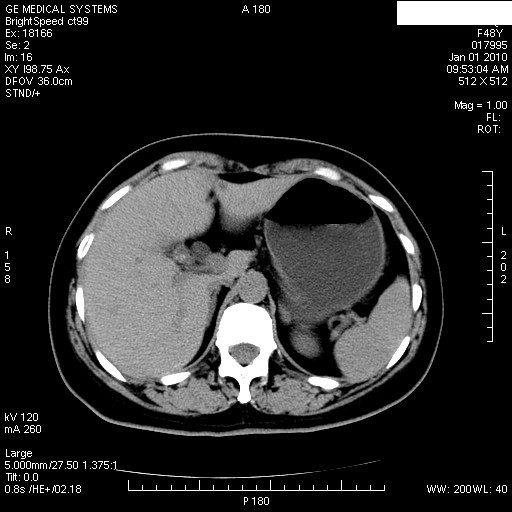

患者女性 48岁 突发上腹部疼痛,无其他不适,查体莫菲氏征阴性,ct示:胆囊炎,胆总管上端轻度扩张

图片如下:

经过抗炎解痉镇痛治疗一周后复查ct如下: